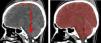

Intracranial volume (ICV) is an important tool in the management of patients undergoing decompressive craniectomy (DC) surgery. The aim of this study was to validate ICV measurement applying the shape-based interpolation (SBI) method using open source software on computed tomography (CT) images.

MethodsThe pre- and post-operative CT images of 55 patients undergoing DC surgery were analyzed. The ICV was measured by segmenting every slice of the CT images, and compared with estimated ICV calculated using the 1-in-10 sampling strategy and processed using the SBI method. An independent t test was conducted to compare the ICV measurements between the two different methods. The calculation using this method was repeated three times for reliability analysis using the intraclass correlations coefficient (ICC). The Bland–Altman plot was used to measure agreement between the methods for both pre- and post-operative ICV measurements.

ResultsThe mean ICV (±SD) were 1341.1±122.1ml (manual) and 1344.11±122.6ml (SBI) for the preoperative CT data. The mean ICV (±SD) were 1396.4±132.4ml (manual) and 1400.53±132.1ml (SBI) for the post-operative CT data. No significant difference was found in ICV measurements using the manual and the SBI methods (p=.983 for pre-op, and p=.960 for post-op). The intrarater ICC showed a significant correlation; ICC=1.00. The Bland–Altman plot showed good agreement between the manual and the SBI method.

ConclusionThe shape-based interpolation method with 1-in-10 sampling strategy gave comparable results in estimating ICV compared to manual segmentation. Thus, this method could be used in clinical settings for rapid, reliable and repeatable ICV estimations.